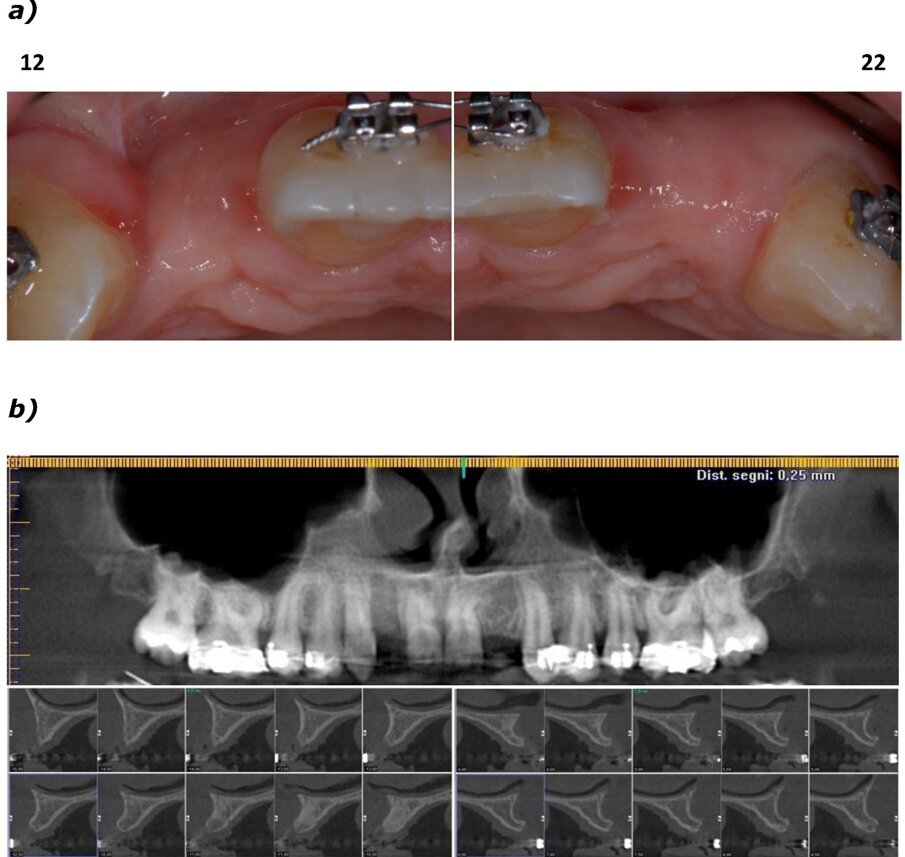

La paziente, donna di 26 anni, presentava agenesia bilaterale degli incisivi laterali superiori. Affermava di voler risolvere la problematica il più velocemente possibile per motivi di natura sia psicologica sia economica, esprimendo il desiderio di ottenere una riabilitazione funzionale ed estetica tramite un intervento finalizzato alla realizzazione di una protesi fissa. È stato quindi prospettato un approccio terapeutico multidisciplinare basato su trattamento ortodontico per migliorare l’allineamento e ottimizzare lo spazio per il posizionamento implantare. Dopo accettazione e firma del consenso, si è proceduto al trattamento ortodontico fisso. In una prima fase, due elementi provvisori a pura funzione estetica sono stati apposti all’apparecchio ortodontico (Fig. 1a). Ottenuto il risultato ortodontico a distanza di 12 mesi (Fig. 1b), si è potuto procedere con l’inserimento di impianti B1ONE (IDI Evolution) a diametro ridotto.

Fig. 1_Presentazione del caso. Il paziente presenta agenesia bilaterale degli incisivi secondari superiori; a) trattamento conservativo con provvisori in resina solidarizzati all’apparecchio ortodontico e a sola funzione estetica; b) trattamento ortodontico per l’ottimizzazione del piano occlusale e dello spazio mesio-distale.